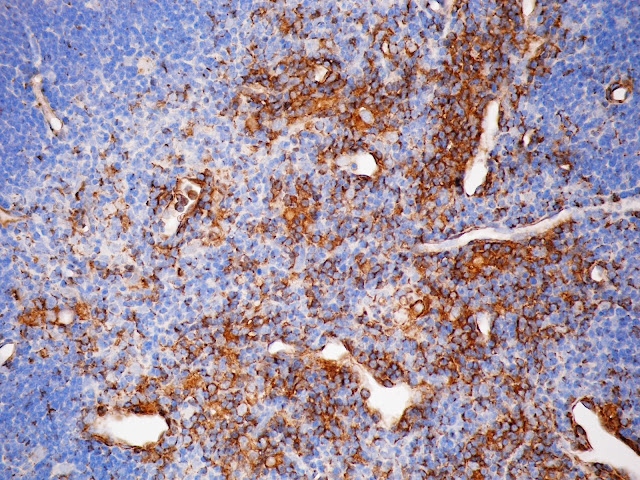

En esta imagen la citoqueratina 8 se ve marcada de color café. La técnica utilizada fue

B. Inmunohistoquímica

Imagen cedida por la M. en C. Martha Luz Ustarroz Cano. Profesora del Departamento de Biología Celular y Tisular. Facultad de Medicina. UNAM